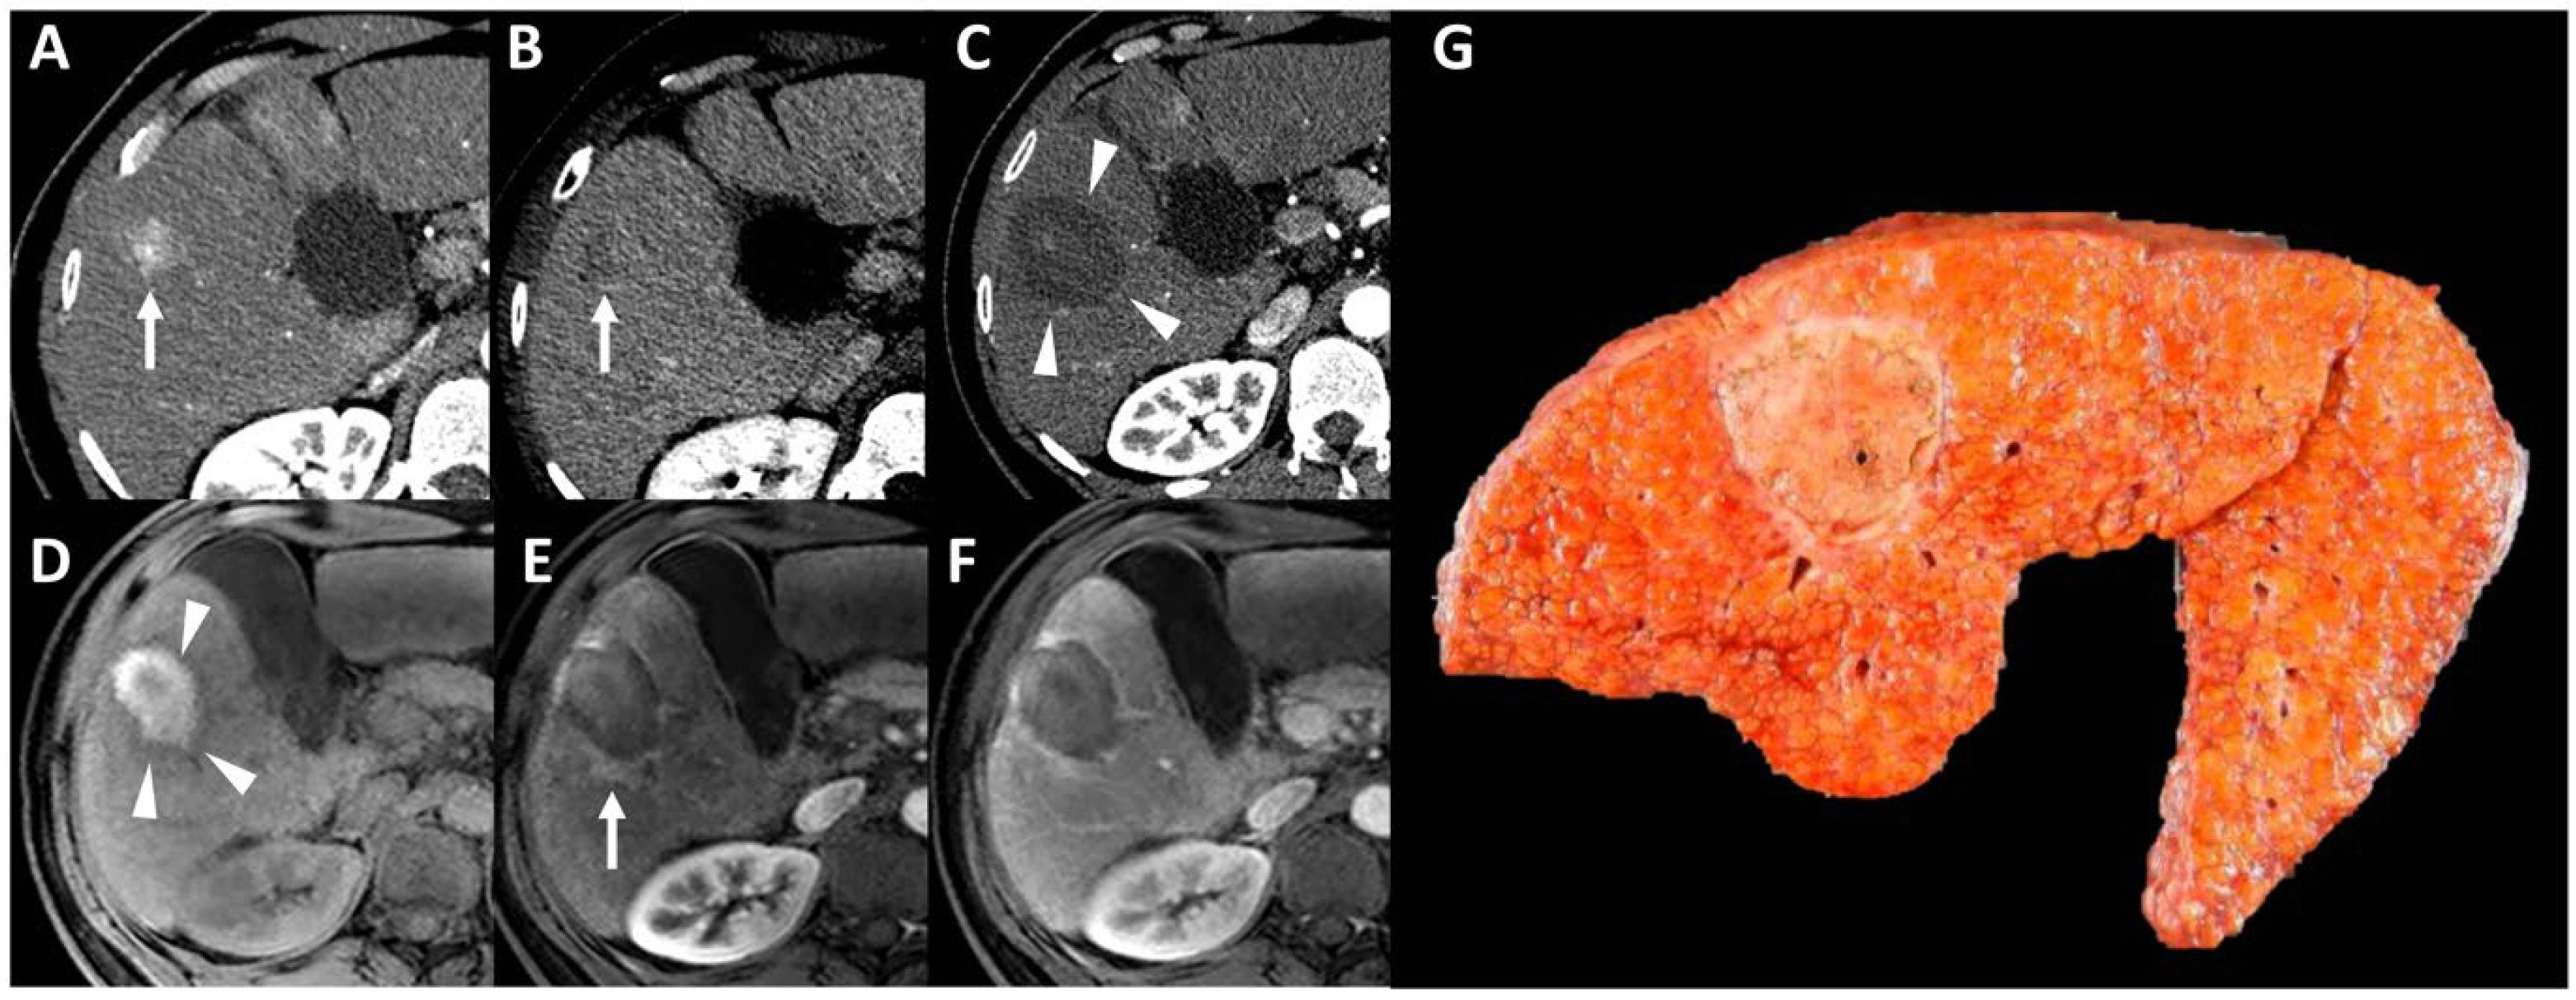

- Dioguardi Burgio, M.; Ronot, M.; Bruno, O.; Francoz, C.; Paradis, V.; Castera, L.; Durand, F.; Soubrane, O.; Vilgrain, V. Correlation of tumor response on computed tomography with pathological necrosis in hepatocellular carcinoma treated by chemoembolization before liver transplantation. Liver Transplant. 2016, 22, 1491–1500. [Google Scholar] [CrossRef] [PubMed]

- Dioguardi Burgio, M.; Sartoris, R.; Libotean, C.; Zappa, M.; Sibert, A.; Vilgrain, V.; Ronot, M. Lipiodol retention pattern after TACE for HCC is a predictor for local progression in lesions with complete response. Cancer Imaging 2019, 19, 75. [Google Scholar] [CrossRef] [PubMed]